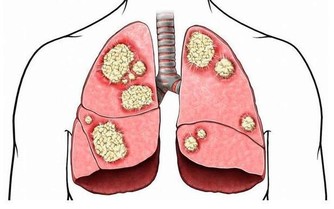

肝臟是人體最大的代謝器官,我們吃進去的食物都需要肝臟進行合成、分解。但肝臟也是很容易「生病」的器官,日常養護十分重要。

中醫認為「養肝就是養命」。如果肝臟代謝不正常,人體所需的養分得不到及時供應,身體各個器官都無法正常工作:本應明亮的眼睛會由於肝血不足而 乾澀 呆滯,本應光滑堅韌的指甲也會幹枯變形。如果肝臟無法正常排毒,毒素就會滯留在體內,再美的女人也會變成「黃臉婆」,再強壯的男人也會萎靡不振。要想身體 好,首先要保護好肝臟,這就是中醫所說的「養肝就是養命」。